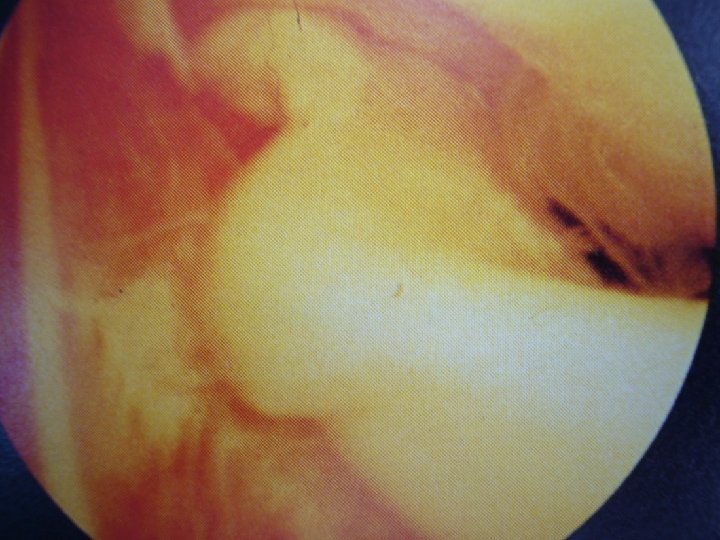

RECHERCHE DU FLEXUM

LE FLEXUM POSTTRAUMATIQUE • • • 1. LE BLOCAGE MENISCAL (VRAI) = Impossibilité d’étendre le genou Aigu ou chronique ou fugace 10 à 30° Flexion conservée Dispense de l’IRM # LE PSEUDO-BLOCAGE Fonctionnel… D’origine rotulienne… Mais attention aux erreurs…